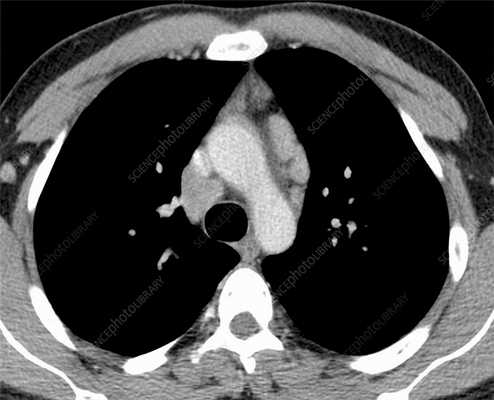

Начальная кардиальная пимфома у пациента с желудочковой аритмией.

Неоднородное утолщение боковой стенки левого желудочка (черные стрелки) из-за проникающего роста лимфомы.

Перикардиальный выпот (белые стрелки) и билатеральный плевральный выпот.